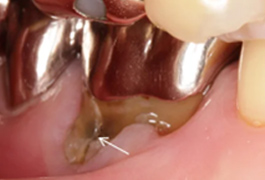

ももこ歯科の精密根管治療は、ペンエンドスタディクラブインジャパンのレギュラーコースで学んだコンセプトに基づいて行なっています。ペンエンドスタディクラブインジャパンのレギュラーコースは、米国で最も古い歯内療法科の一つであるペンシルバニア大学歯内療法科の大学院プログラムをコンパクトにまとめたもので、1年間日本で学べます。このプログラムの講師陣が最重要項目だ、と強調されていたことは、精密根管治療における診査診断と意思決定力です。診査診断と意思決定力が養われてこそ、精密根管治療の技術が向上します。

大きな虫歯で神経をとった方がいい(根管治療を受けた方がいい)といわれた方は、精密根管治療を受けるとその後の歯の状態にトラブルが少なく有意義だと思います。それから、抜歯を提案された方、根管治療がなかなか終わらず不安を抱えていらっしゃる場合、どうしても歯を残したいというご希望がある方は、ぜひ一度ももこ歯科にご連絡ださい。かかりつけ医がいて、根管治療をももこ歯科で受けたい方、セカンドオピニオンをご希望の患者様は紹介状持参でお願いしています。